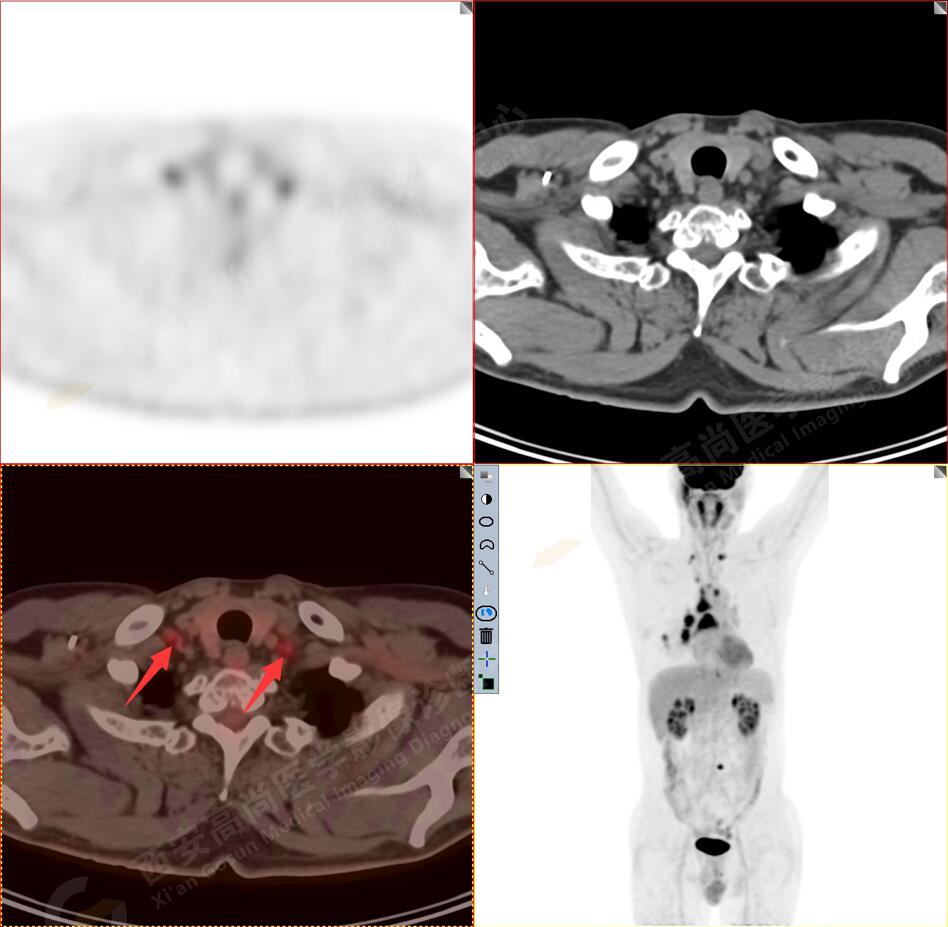

2.以下為全身多發(fā)轉(zhuǎn)移灶

3.右側(cè)肺門、縱隔(1L、1R、3A、4、6、7組)及雙側(cè)鎖骨上多發(fā)腫大淋巴結(jié),呈不同程度FDG代謝異常增高,考慮為淋巴結(jié)轉(zhuǎn)移。